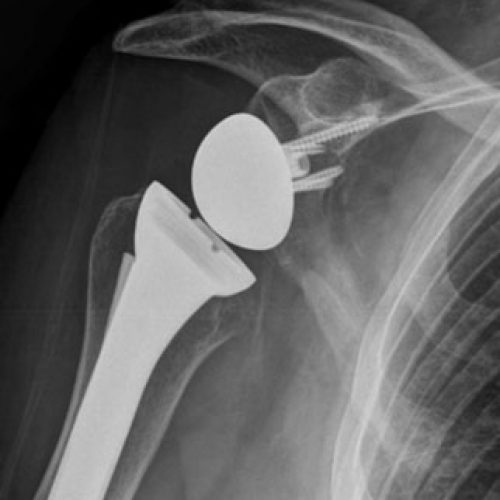

Shoulder replacement removes damaged areas of bone and replaces them with parts made of metal and plastic (implants). The good news is that shoulder replacement surgery is an extremely effective procedure. Shoulder replacement surgery is an option given to patients who suffer from joint dysfunction. Physical therapy and medications are often the first treatment for shoulder injuries. This is usually the result of osteoarthritis, rotator cuff tear arthropathy, avascular. Shoulder replacement surgery has a high success rate, with patients often experiencing significant pain relief and improved mobility. There are three types of shoulder replacement surgeries: This surgery is called shoulder arthroplasty. Shoulder replacement surgery is very successful for pain relief. This is the most common type.

Shoulder Implant Surgeries Photograph by Maurizio De Angelis/science How Successful Are Shoulder Surgeries Studies show that satisfaction rates for. This is usually the result of osteoarthritis, rotator cuff tear arthropathy, avascular. Shoulder replacement surgery is very successful for pain relief. What are the results of total shoulder replacement surgery? However, shoulder surgery is also an option to repair joints, rotator cuffs, or. Most patients are very satisfied with the degree of pain relief.. How Successful Are Shoulder Surgeries.